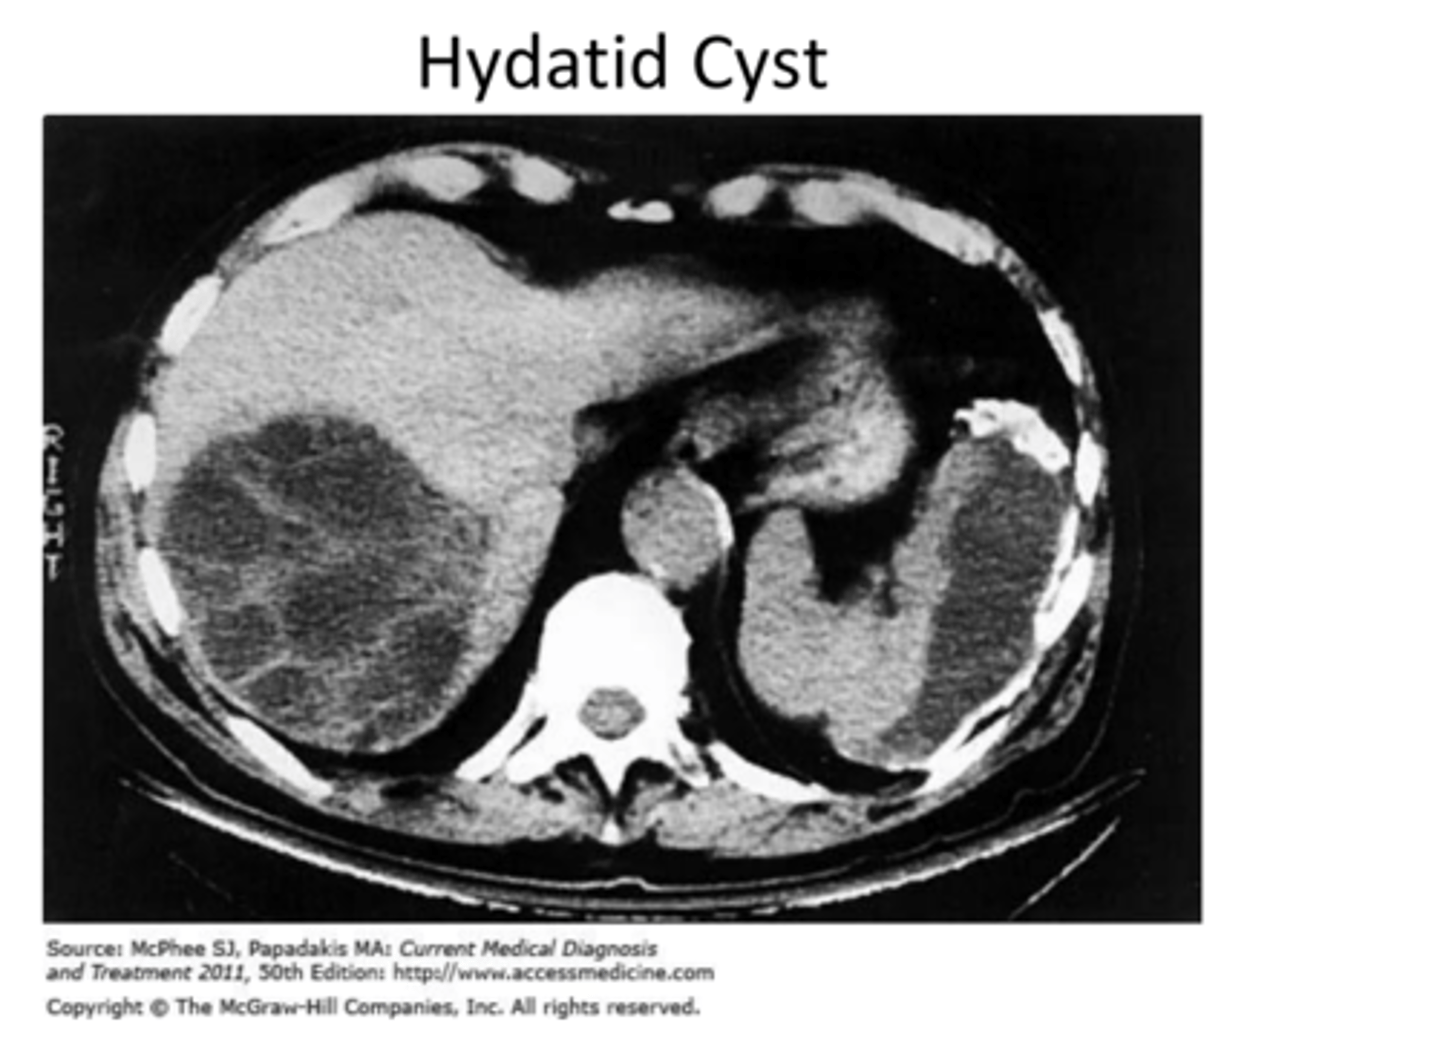

Hyatid disease

How to diagnoses Hyatid disease from dog tapeworms

Look for lesions on xray for hyatid cysts/eggs